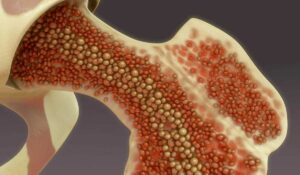

El mieloma múltiple (MM) es un tipo de cáncer que afecta las células plasmáticas en la médula ósea, comprometiendo el sistema inmunológico y provocando complicaciones graves como anemia, problemas renales, lesiones óseas e infecciones recurrentes. Según datos de Globocan 2022, en México se registraron 2,346 nuevos casos de esta enfermedad, con una prevalencia de 7,026 personas viviendo con MM.